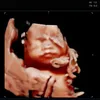

@bernadettecaffreyxwright:

Oh my days 😍😍😍😍😍😍

😍😍😍

Now. That’s something to be proud of 🤭🤭